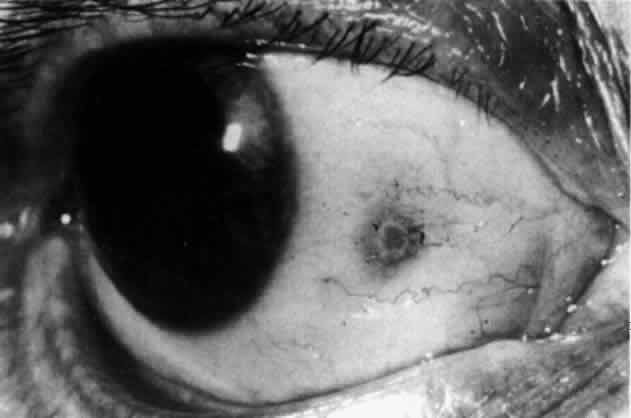

episcleritis and nodular episcleritis. ETIOLOGY Thirty percent of patients with episcleritis had some associated general conditions,6–8 but the rest defied all attempts to discover an etiology. Although some patients had a strong family history of atopy, results of patch and prick testing were uniformly negative. Of those in whom an etiology was found, only 5% showed any association with collagen disease, 7% had an association with herpes zoster, and 3% each had an association with gout or syphilis; the rest had associated conditions such as erythema nodosum, Schönlein-Henoch purpura, erythema multiforme, contact with industrial solvents, or penicillin sensitivity, indicating an immune basis for the condition. PATHOLOGY Microscopic and electron microscopic studies of biopsy specimens from patients with simple and nodular episcleritis have been totally noncontributory in the attempt to discover the etiology of this condition. The inflamed area is packed with lymphocytes and a few other inflammatory cells, but there are no mast cells, plasma cells, or eosinophils. CLINICAL MANIFESTATIONS The onset is usually acute; the eye may become red and painful in as short a time as half an hour. The patient's main complaint is redness of the eye, which is often sectorial and may be accompanied by a feeling of hotness, pricking, and mild discomfort. There is no discharge, although the eye waters occasionally. Pain may be absent, but the discomfort may be so severe that patients cannot pursue their normal occupation. The pain is localized to the eye, rarely radiating to the forehead and never producing the severe boring pain that is so commonly described in scleritis. In a severe attack the lids may become swollen, but this is a rare occurrence. If photophobia is present, an accompanying corneal condition should be suspected. Simple and nodular episcleritis differ in their clinical courses, but in both the edema and infiltration are entirely within the episcleral tissues. The sclera is not involved. The maximum congestion is in the superficial episcleral network, with some slight congestion of the conjunctival vessels and deep episcleral vessels (Fig. 10). The intraocular structures are not involved in either variety, nor is the visual acuity affected. Anterior segment fluorescein angiography reveals a normal vascular pattern but a very rapid flow rate, with the whole transit of the dye being completed within 2 or 3 seconds (Figs. 11 and 12).

The redness of simple episcleritis may be intense, varying from a fiery-red or a brick-red discoloration to a mild red flush, but it does not have the bluish tinge that is seen in scleritis. The distribution is usually sectorial but can involve the whole anterior segment of the globe. The episcleral vessels are engorged but retain their normal radial position and architecture (Figs. 13 and 14; Color Plate 1A). In simple episcleritis, there is a diffuse edema of the episcleral tissues. These tissues are sometimes infiltrated with gray deposits that appear yellow in red-free light. Surprisingly, the eye is rarely tender to the touch.

In contrast to simple episcleritis, the infiltration and edema of nodular episcleritis are localized to one part of the globe, forming a nodule and some surrounding congestion (Color Plate 1B). The nodule can be moved over the underlying sclera, which is not edematous. The scleral plexus of vessels can be distinguished deep to the nodule, lying flat on the sclera and slightly congested but otherwise normal in color and configuration (Figs. 15 and 16). Episcleral nodules may be single or multiple but do not undergo necrosis (see Fig. 16). After multiple attacks of nodular episcleritis in the same location, the superficial lamellae of the sclera show some alteration and become slightly more transparent in this one area. TREATMENT Even without therapy, simple episcleritis improves considerably within the first week and resolves within 3 weeks (Fig. 17). Provided the eye is not too uncomfortable, most patients can be persuaded to leave the eye untreated, because the condition will resolve spontaneously. However, if it is believed that some treatment is desirable, topical corticosteroids or locally applied nonsteroidal anti-inflammatory drugs (NSAIDs) may make the eye more comfortable and speed resolution slightly (see Fig. 17).9 Use of corticosteroid drops must be continued for several days after the inflammation has subsided to prevent the exacerbation of the condition that occurs if they are stopped suddenly. Prednisolone, betamethasone, or dexamethasone drops may be administered hourly until redness disappears, and then three times daily for 4 to 5 days. Under no circumstances should topical steroids be administered continually for more than a few weeks at a time because of the very real danger of inducing steroid glaucoma and cataract. If the condition fails to respond immediately, other treatment regimens should be sought. Ocular NSAIDs can be administered four times daily until redness disappears. Glaucoma and cataract have not been observed after prolonged use, but many patients become intolerant to the use of the ointment or complain of stinging and irritation. Whereas simple episcleritis resolves rapidly without therapy, the resolution of nodular episcleritis is much slower. Local therapy is consequently of much more value; the same regimen of treatment is followed. In the few patients in whom episcleritis becomes indolent, or in whom recurrences are so numerous that the patient becomes incapacitated, it is reasonable to consider systemic therapy with NSAIDs such as flurbiprofen (Froben), 100 mg three times daily, which usually gives immediate and prolonged relief of symptoms and signs. It is important to note that not all of the NSAIDs work in this condition. Treatment may be terminated abruptly when the condition comes under control. The complications of episcleritis are minor and are not responsible for any decrease in visual acuity. COURSE AND PROGNOSIS Whether treated or not, simple episcleritis will resolve in 10 to 21 days. It will usually reappear at irregular intervals and then eventually disappear. An accurate 12-month record kept by a patient who went without treatment is shown in Figure 18. He was free from any further attacks for 3 years. He then had four attacks in the next 3 months and has had none since. No etiologic or precipitating factor has been found. In nodular episcleritis, the nodule initially increases rapidly in size, sometimes reaching the size of a split pea. Thereafter it gradually regresses over a variable period and eventually disappears, although this may take up to 2 months without treatment. Recurrences occur also in nodular episcleritis, but the two varieties are not mutually exclusive (a simple episcleritis may recur as a nodular episcleritis and vice versa). However, episcleritis never develops into scleritis in the same attack, although it invariably accompanies scleritis. Of 180 patients initially diagnosed as having episcleritis, only 4 developed scleral involvement.10 Episcleritis is an entirely benign condition, although it may be a great nuisance to the patient. It may recur over a period of many years, but it rarely leaves any residual ocular changes except for some areas of scleral transparency or localized stromal keratitis in those patients who have had severe attacks of nodular disease occurring always at the same site. Of 180 patients analyzed,10 only 2% had a decrease in visual acuity of two lines or more within a year of the onset, and in every case this was from increasing involutional cataract. |